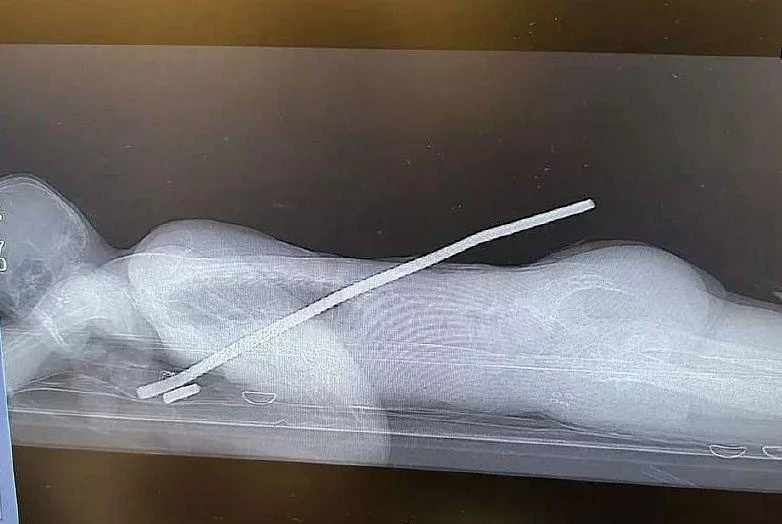

В августе 2021 года 69-летний Дэвид Уэллс кушал стейк и подавился

В результате он упал в обморок и перестал дышать. Мужчину в экстренном порядке госпитализировали. Его подключили к аппарату жизнеобеспечения, благодаря которому он дышал, но мозг его перестал функционировать.